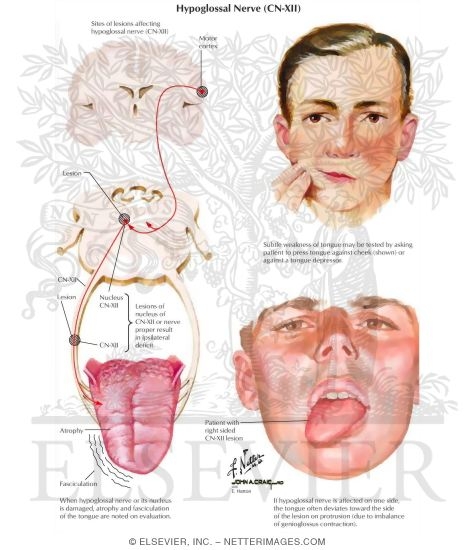

Hypoglossal Nerve (CN-XII)

Hypoglossal Nerve (CN-XII)

Hypoglossal Nerve (CN-XII)

Hypoglossal Nerve (CN-XII)